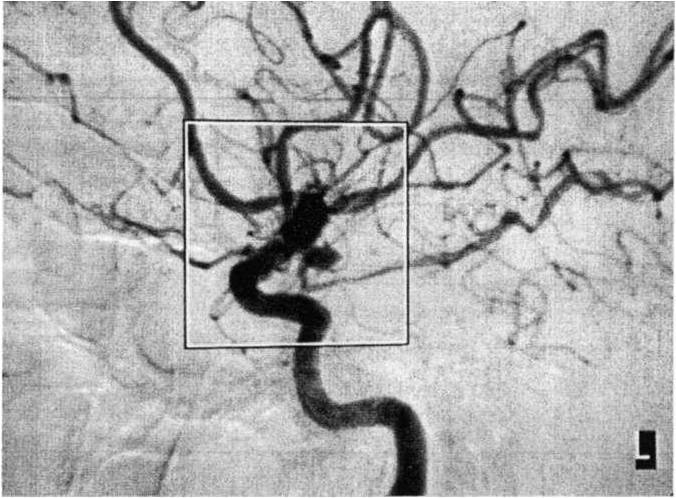

Scenario: A 54-year-old female was taken to an emergency

room after collapsing at work. She was alert and communicative,

with a severe headache, photophobia, nuchal rigidity,

and blurry vision. Computed tomography (CT) of the brain

revealed diffuse subarachnoid blood in the basal cisterns,

mild hydrocephalus, and no intraparenchymal hematoma.

Her angiogram is depicted below